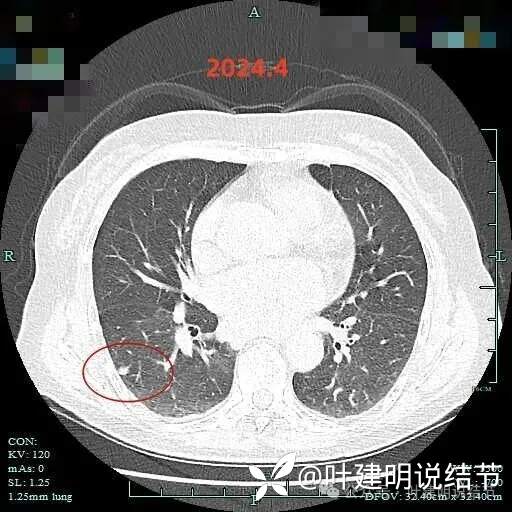

2024年4月右下病灶血管进入明显,整体密度显高,表面稍不平,欠光滑。